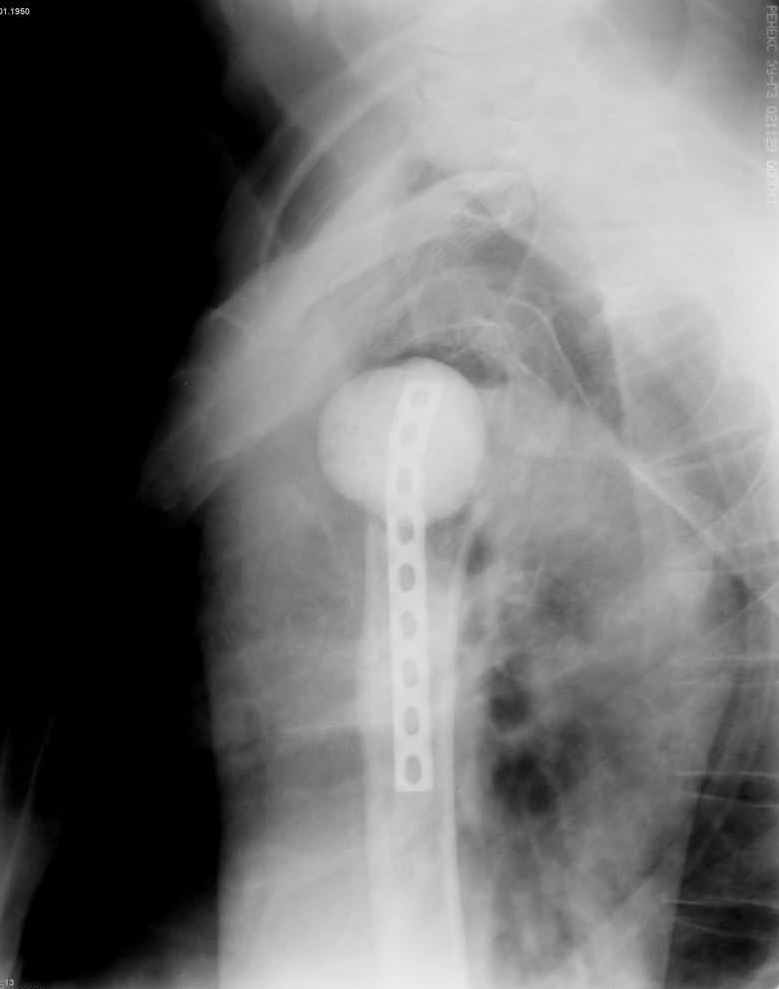

Имя     : 5.jpg

Тип     : image/jpeg

Размер  : 51844 байтов

Описание: отсутствует

Url     : http://weborto.net:8080/pipermail/ortho/attachments/20070925/75bce6d9/attachment-0012.jpg